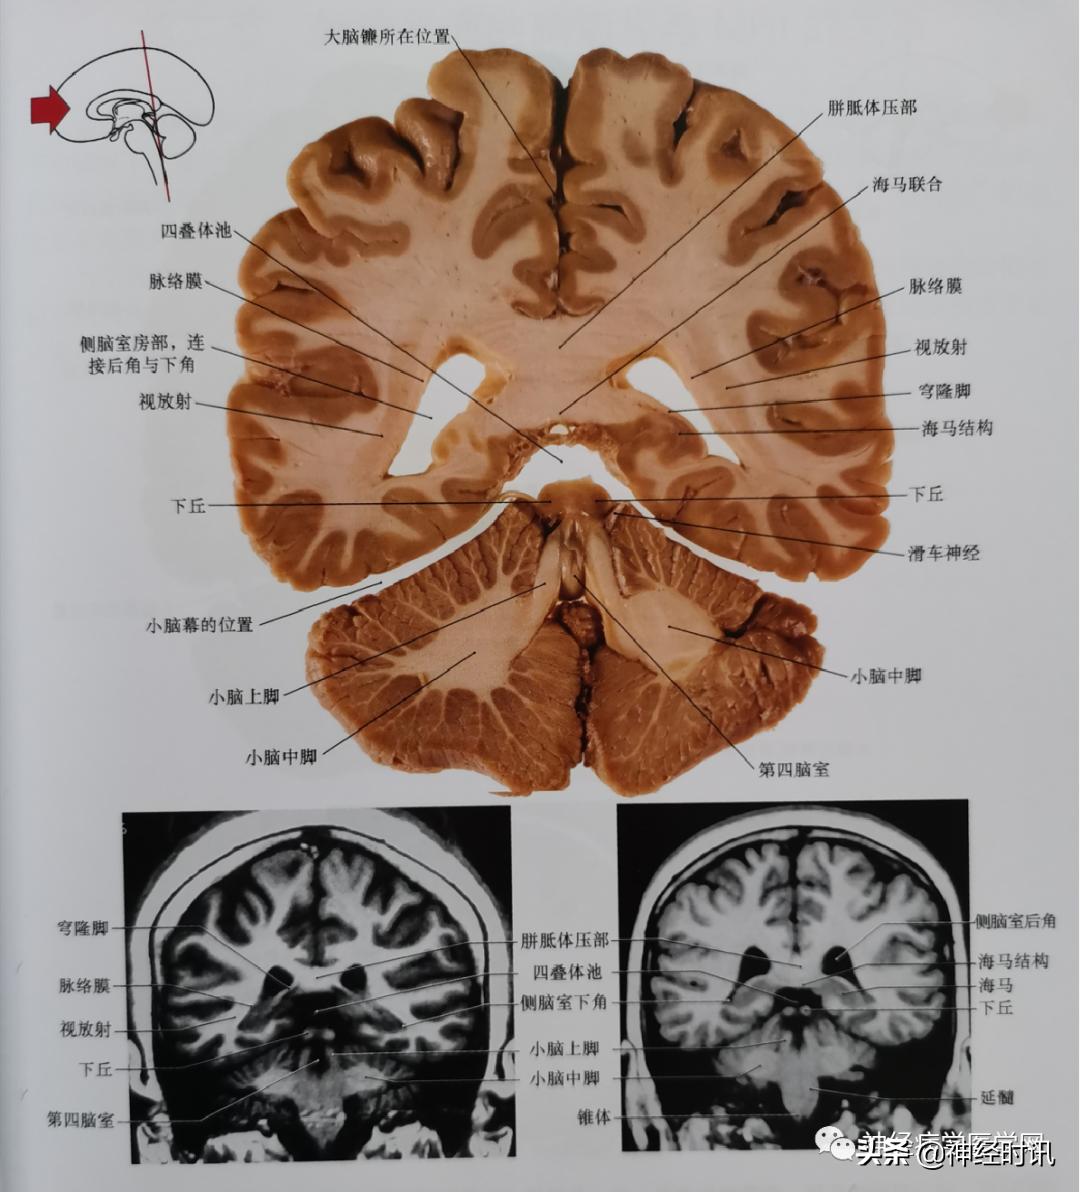

图7 通过松果体、丘脑枕的尾部、上丘、脑干被盖、小脑中脚平面的冠状位影像。注意小脑中脚的特征及毗邻关系

图8 通过胼胝体压部、四叠体池的尾部、侧脑室三角区、小脑上脚、小脑中脚、第四脑室中部平面的冠状位影像。注意下丘与四叠体池的关系。